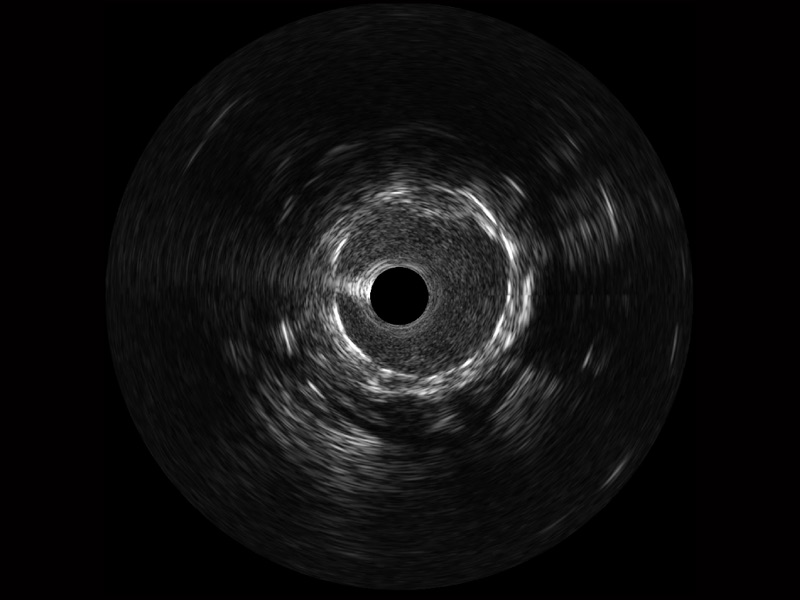

新葡的京集团8814检测站宽频IVUS图像

传统IVUS图像

对比传统IVUS导管成像,新葡的京集团8814检测站宽频IVUS图像的近场支架梁显影更细腻,远场中膜外血管仍清晰可辨,兼顾远中近,兼顾分辨力与穿透深度